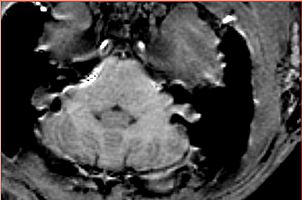

Fat shift artifact significantly obstructs the cortex in the occipital lobe for all subjects